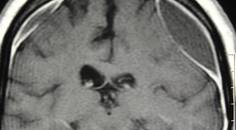

02/12/2024 - Medical NewsBlocking Artery Supplying the Brain Covering After Subdural Hematoma Reduced Repeat Surgery